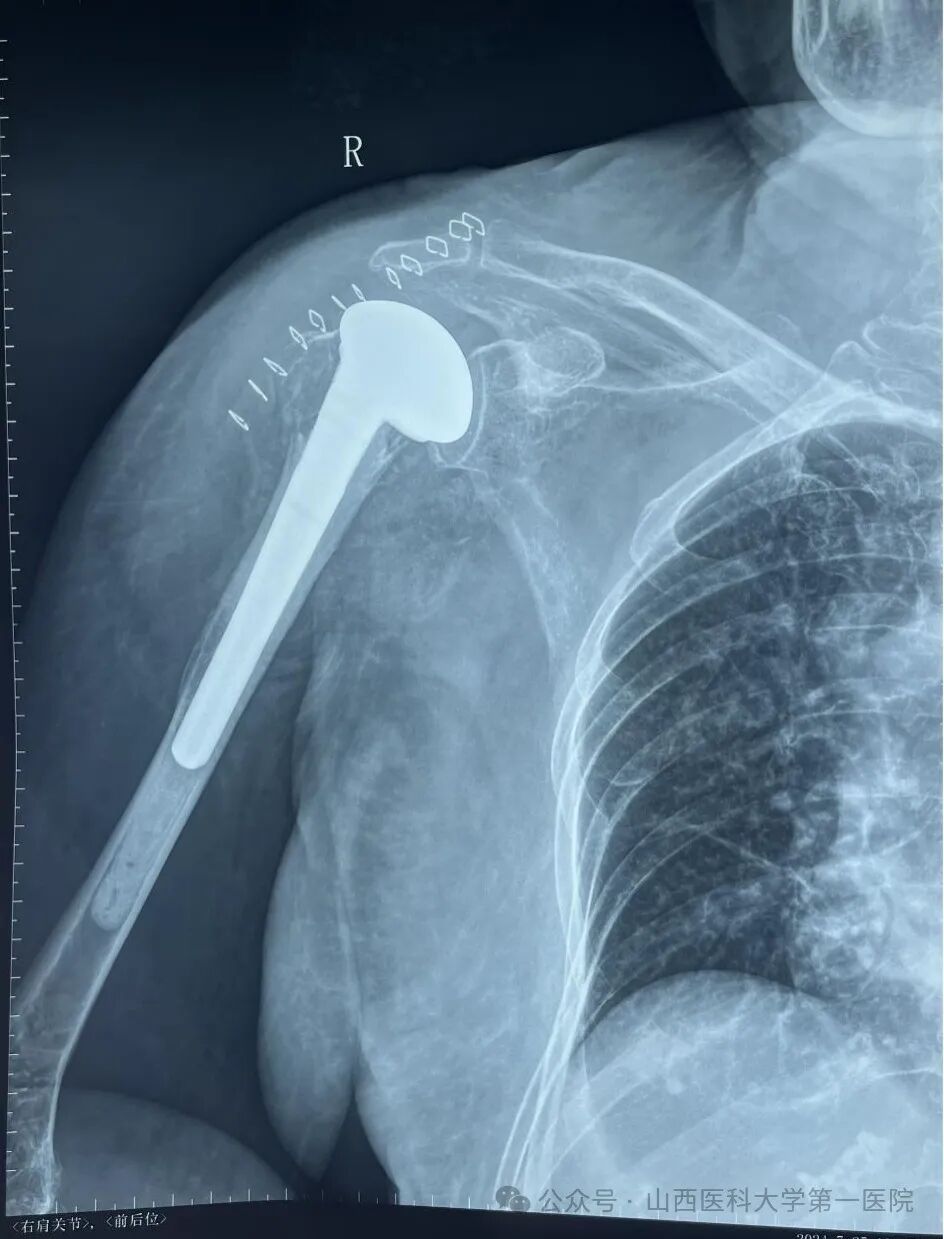

术中,杨自权主任团队在麻醉科、手术室的协助下,采用了长约仅仅7cm的手术切口显露骨折断端,标记肱二头肌长头肌腱及肩袖组织后,完整取出肱骨头,保证后倾角后选择合适高度假体试模,试模满意后安装假体并重建肩袖及肱二头肌长头肌腱,重建后的肩袖组织完美覆盖肱骨头,手术成功。

术后x线

人工肱骨头假体置换是治疗复杂肱骨近端骨折的有效手段之一,适用于肱骨近端粉碎骨折、骨关节炎、肩袖撕裂关节病患者,不仅可以更快恢复患者肩关节功能,而且可以减少传统内固定手术后骨折不愈合、肱骨头坏死等并发症的发生。